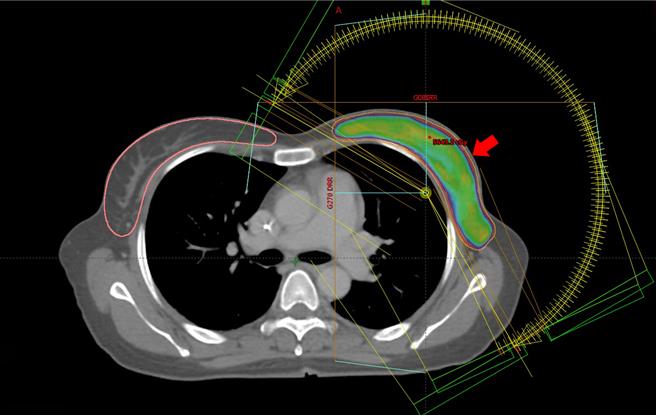

手术后进行化疗治疗后,也安排放射治疗,避免以后復发,许维中表示,在接受光子刀放射治疗时,特别跟她做放射治疗皮肤照护的卫教,并利用电脑精准运算,将放射剂量调控在安全又有效的范围,每周进行5次光子刀治疗,完成25次的疗程后,不但没有破坏她的刺青,目前追踪检查也无癌细胞踪迹。

许维中强调,乳癌术后的放射线治疗,不但精准追杀术后可能残留的癌细胞,也可以降低局部乳癌復发的风险。尤其,当癌细胞已转移腋下淋巴,针对淋巴区域进行放射治疗更是重要。